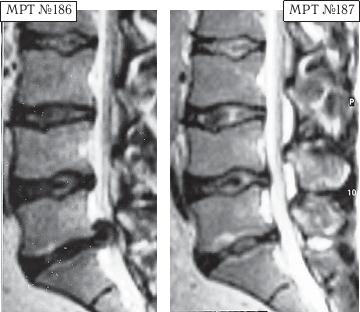

МРТ № 4

МРТ № 5

На МРТ № 4 наблюдается межпозвонковый диск в начальной стадии развития дегенеративно-дистрофического процесса.

На МРТ № 5 наблюдается межпозвонковый диск на более поздней стадии развития дегенеративно-дистрофического процесса.